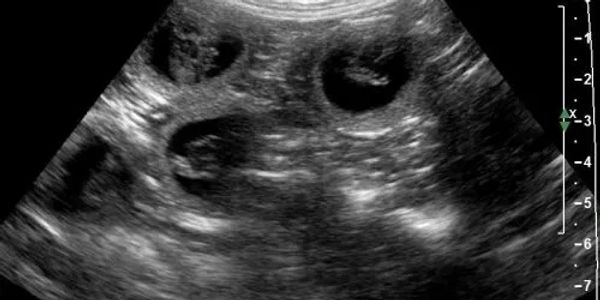

This is our preferred diagnostic to ensure proper timing.